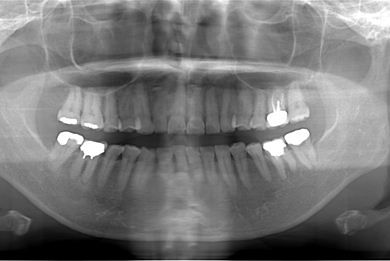

部分矯正治療+セラミック治療

| 性別/年齢 | 女性 / 54歳 | ||||||||||||||||||||||||||||||||

| 主訴 | 下の前歯のゆがみが気になり、相談。 | ||||||||||||||||||||||||||||||||

| 治療方針 | 上顎前歯の叢生を部分矯正にて審美的回復を行い、上顎前歯はラミネートベニアにて審美的回復を行う。 | ||||||||||||||||||||||||||||||||

| 治療内容 | 唇側部分矯正(ホワイト)、オールセラミックラミネートベニア8本 | ||||||||||||||||||||||||||||||||

| 総治療費 | 1,361,063円 | ||||||||||||||||||||||||||||||||

| 治療期間 | 2ヶ月 |